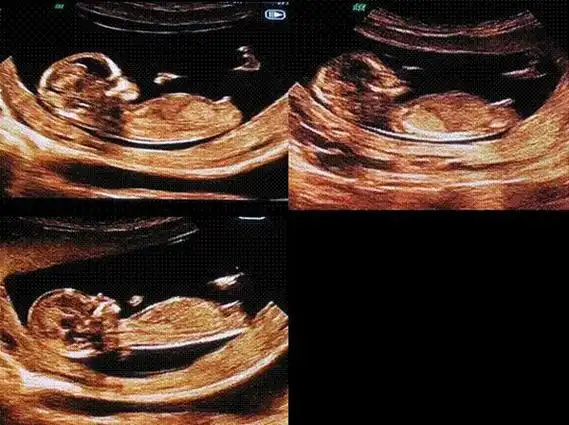

生了女孩的nt图片弯着就是男孩平是女孩吗2

是不是所有的nt图像,有三条线的都表示生女孩呢?

如果nt图是弯着的生男孩,nt图是平行的生女孩